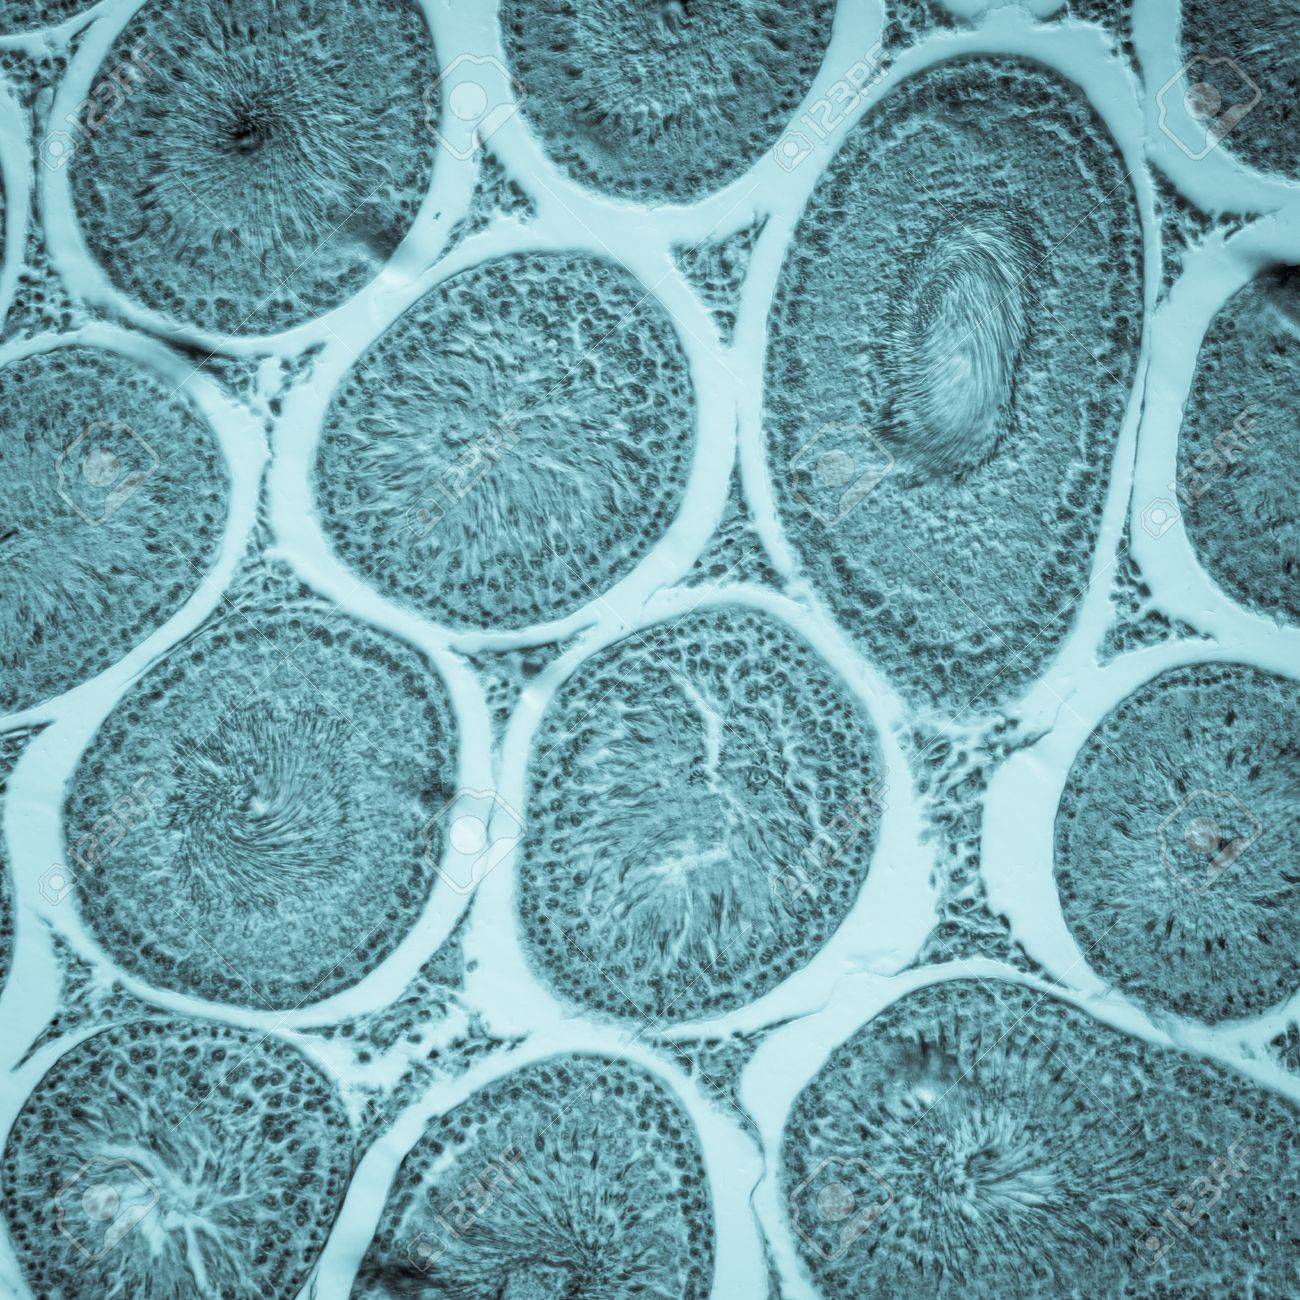

anatomy, aniaml, background, biology, cell, clinical, education, egg, female, fertility, health, healthcare, histology, horizontal, human, life, macro, magnification, medical, medicine, micro, microscope, microscopic section, mouse, oocyte, organism, ovary, ovulation, panorama, parent, photograph, photomicrograph, physiology, pink, pregnancy, purple, rat, red, reproductive, research, science, sex, slice, small, uterus,